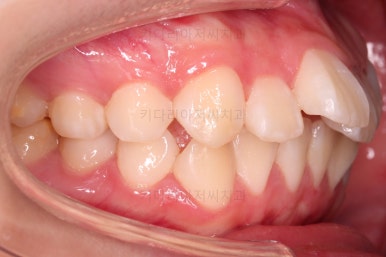

부산덧니교정 마무리를 한 모습인데요.

가지런한 모습 좋고, 교합이나 중앙선 등 매우 잘 맞네요.

전후를 비교해 볼게요.

치열, 교합, 악궁의 형태 매우 좋아졌어요.

입이 매우 나와있을 때 턱끝에 힘이 들어가는 습관이 아직 개선되지 못했는데 힘 빼고 다무는 연습을 좀만 더 해준다면 옆라인도 훨씬 좋아질 것 같았어요.

전반적으로 만족스러운 치료였습니다.